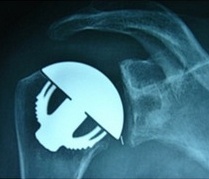

Luxation gléno humérale

- la luxation de l'épaule est une perte de la relation entre les surfaces articulaires de l'humérus et de la glène de l'omoplate (scapula), elles sont fréquentes